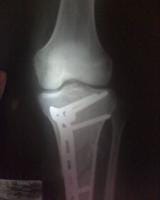

Fractura metafisiaria de tibia izquierda..

Doctor mi nombre es soy de la ciudad de Caracas Venezuela tengo 19 años de edad queria hacerle unas cuantas preguntas con respecto a mi fractura como lo indica el titulo una fractura metafisiaria de tibia izquierda el dia 01/01/09 ingrese al hospital y me indicaron que tenia que quedar internado hospitalizado durante 1 mes espere la operacion el dia 28/01/09 me operaron se me realizo una reduccion mas fijacion interna con placa lcp 4,5++ ingerto oseo en fisura de tibuia izquierda evolucione de forma satisfactoria y fui dado de alta el dia 30/01/09 acudi a control en el hospital pero devido a que me plantearon retiro de tornillo proximal, les plantie que necesitaba consultar con otros traumatologos y me indicaron que no era necesario devido a eso me retire del hospital y acudi a otro centro cree usted que sea el tipo de placa indicado el que me colocaron?.

Durante este tiempo los demas traumatologos me decian que no era necesario ya que la palca no presentaba rechazo, pero con respecto a eso doctor queria hacerle una pregunta tengo mi pierna hinchada en la parte inferior de la placa es visible la placa se puede palpar los tornillos mucho mas que antes.. Hace aproximadamente empeze a afincar sin amuletas y camino bien pero al caminar mucho se me hincha la pierna y me duele mucho espero que me ayude tengo algunas fotos que se las dejare a continuacion para que usted opine al respecto tengo tiempo que no me tomo algunas placas pero recientemente me hare una.. La cicatriz presenta una protuberancia al afincar solo se ve la protuberancia pero al dejar de afincar desaparece como una pelota que piensa usted al respecto? ¿Esto me ha sido un problema devido a que no he trabajado devido a que se me complica usted cree que pueda estar presentando un rechazo de la placa? ¿Termine mis terapias efectivamente y se me plantea reanudarlas usted cree que sea indicado? O ir al gimnacio a ejercitar la pierna los musculos.. Espero su pronta respuesta muchas gracias dr..